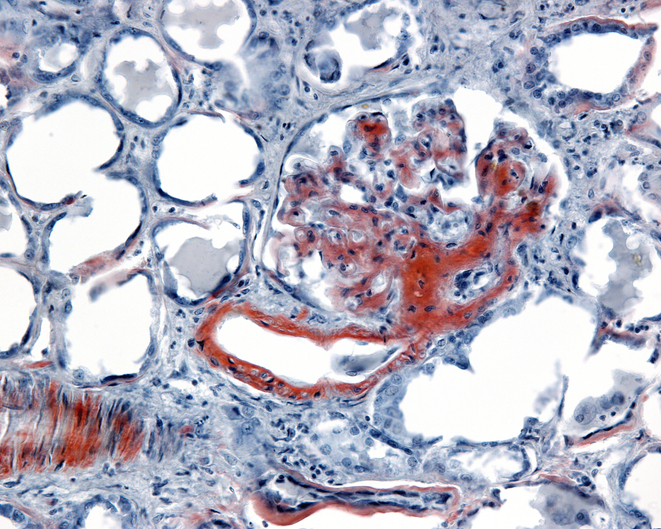

A case study highlights the importance of avoiding anchoring bias in the diagnosis of cardiac amyloidosis.

The diagnosis of AL amyloidosis requires a high index of suspicion to render a prompt diagnosis and appropriate treatment.

People with amyloidosis have a significantly higher prevalence of atrial fibrillation.